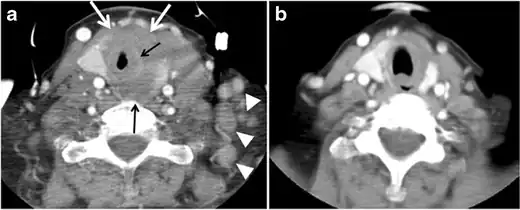

Fig. 11. Thyroid non-Hodgkin's large B-cell lymphoma in a 66-year-old female patient. an Axial enhanced neck CT scan demonstrates left thyroid lobe and isthmus homogeneously hypodense and minimally enhancing mass (white arrows). This lesion invades the prevertebral muscles (black arrows). Note the multiple enlarged level V lymph nodes (white arrowheads). b Post-treatment image shows significant reduction in size and mass effect of the left thyroid infiltrative mass, with almost complete resolution of the left cervical lymphadenopathy.[1] -

Fig. 12. Diffuse thyroid large B-cell lymphoma in a 79-year-old female patient. an Axial enhanced neck CT scan demonstrates a homogeneously hypodense and minimally enhancing large right thyroid solid mass (long white arrow) extending into the thyroid isthmus. It is encasing the right carotid artery (short white arrow) and displacing of the trachea and oesophagus to the left side.[1]

Thyroid lymphoma

Thyroid lymphoma represents about 5% of thyroid malignancies. Non-Hodgkin's lymphoma is the most common type and can be secondary to generalized lymphoma or a primary tumour. Primary thyroid lymphoma usually pre-exists with Hashimoto's thyroiditis. On CT scans with and without contrast, lymphomas tend to have low attenuation values. Thyroid lymphomas have a variable appearance and mostly manifest as a solitary mass (80%). They may also manifest as multiple nodules (15% to 20%) or as a bulky mass replacing the entire gland with extra-thyroid extension (Figs. 11 and and12).12). The presence of cervical lymphadenopathy supports such a diagnosis. Although it is uncommon, tumour necrosis has been reported.[1]